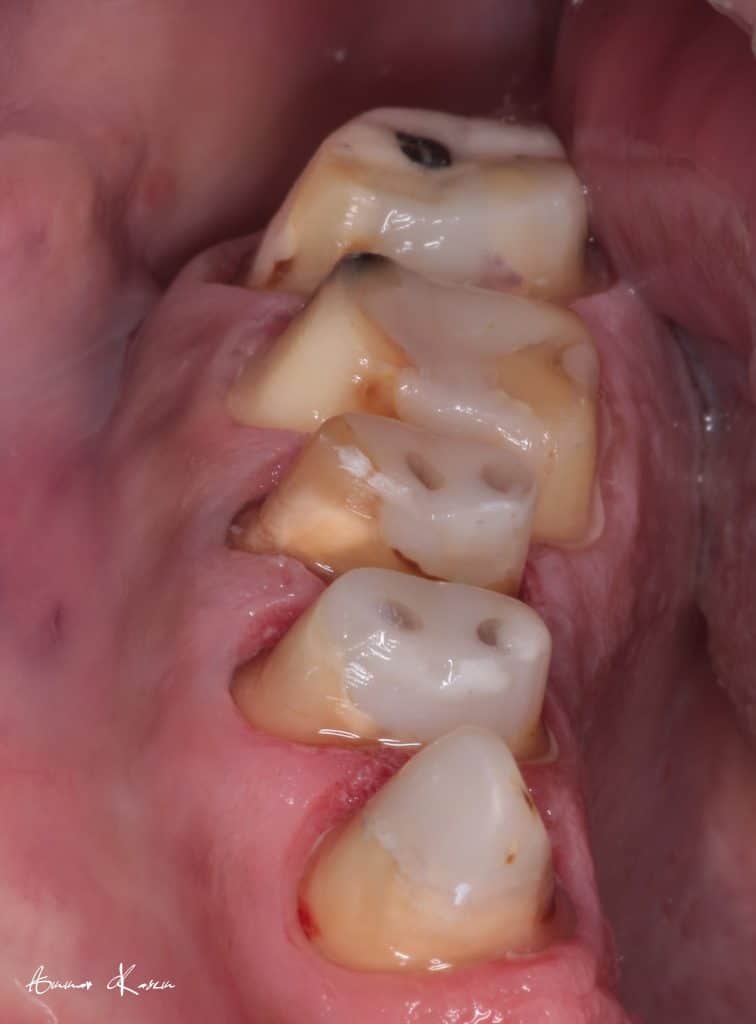

35 years old male patient having old PFM restorations

The patient was normally class I occlusion type ( according to old photos and cephalometric analysis) till he received this defective restorations 10 years ago

With time, the mandible shifted till become habitual class III